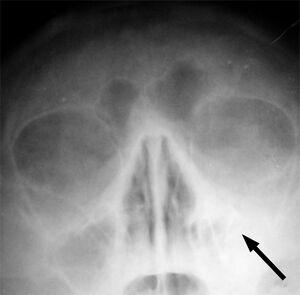

| يشير السهم إلى منطقة الالتهاب في جيوب الفك العلوي في الجانب الأيسر من الوجه. لاحظ أن المنطقة التى يشير لها السهم ليست شفافه لقلة الهواء فيها، مما يشير إلى امتلائها بالسوائل بالمقارنه مع الجانب الآخر من الوجه. | |